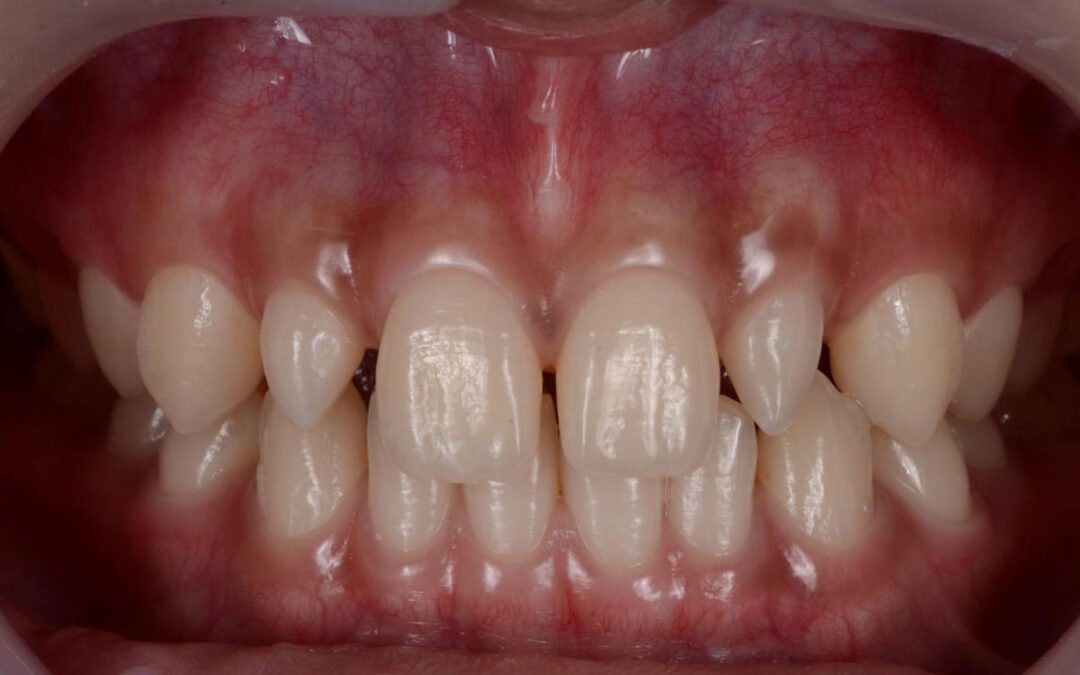

Casos mais extensos: quando o desgaste é generalizado

Em situações de desgaste severo — como em pacientes com bruxismo intenso ou erosão crônica — pode ser necessário um planejamento reabilitador mais amplo. Isso pode envolver:

- Facetas

- Onlays ou overlays em cerâmica

- Reabilitação oclusal completa

Nesses casos, o objetivo não é apenas restaurar dentes isolados, mas reorganizar função, estética e equilíbrio oclusal.